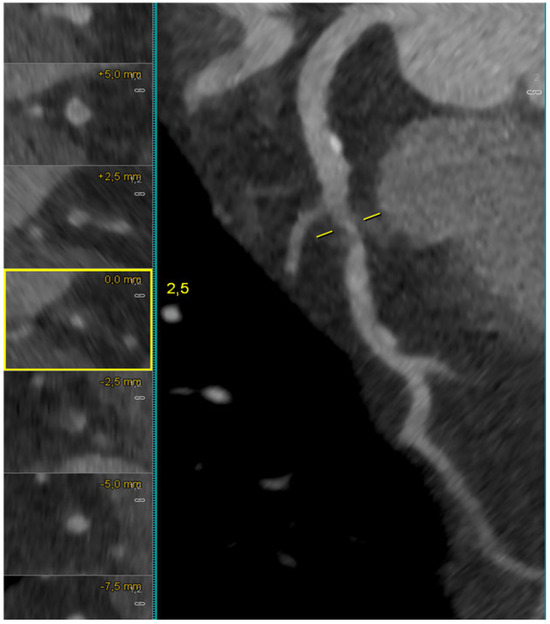

Figure 6 illustrates a calcified LAD–D1 bifurcation lesion, where long-axis and cross-sectional MPR views demonstrate semi-circumferential calcium distribution, allowing for the semiquantitative assessment of the calcific burden. The complementary MIP reconstruction highlights the extent of calcification across the bifurcation segment.

Figure 6.

CCTA evaluation of a heavily calcified LAD–D1 bifurcation lesion. Long-axis MPR reconstruction of the left anterior descending artery (LAD) shows an extended calcified plaque involving the proximal and mid segments, with an additional MPR view illustrating severe calcification across the LAD–first diagonal (D1) bifurcation. The MIP CCTA reconstruction further highlights the complex and heavily calcified morphology of the lesion. Abbreviations: LAD, left anterior descending; D1, first diagonal; MPR, multiplanar reconstruction; MIP, maximum intensity projection; CCTA, coronary computed tomography angiography.